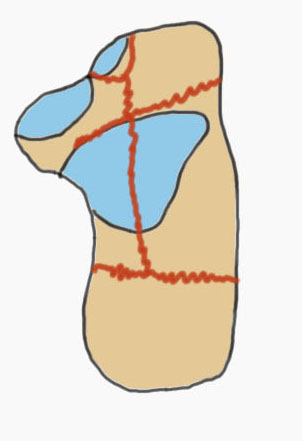

Fracture patterns

| Primary fracture line | Secondary fracture lines |

|---|---|

|

Lateral process of talus driven into crucial angle - starts at lateral wall near tarsal sinus - passes obliquely across posterior facet - exits at medial wall posterior to sustentaculum tali |

Passes immediately behind the posterior facet of the subtalar joint - exits posterior to posterior facet & anterior to tendoachilles insertion - creates thalamic portion containing posterior facet |

Common fracture fragments

| Sustenacular | Superolateral | Lateral wall | Posterior tuberosity |

|---|---|---|---|

| Superomedial |

Lateral fragment of posterior facet

|

Tongue fracture | |

| Attached to talus by deltoid ligament | Thalamic fragement | Secondary fracture line exits below tendoachilles |